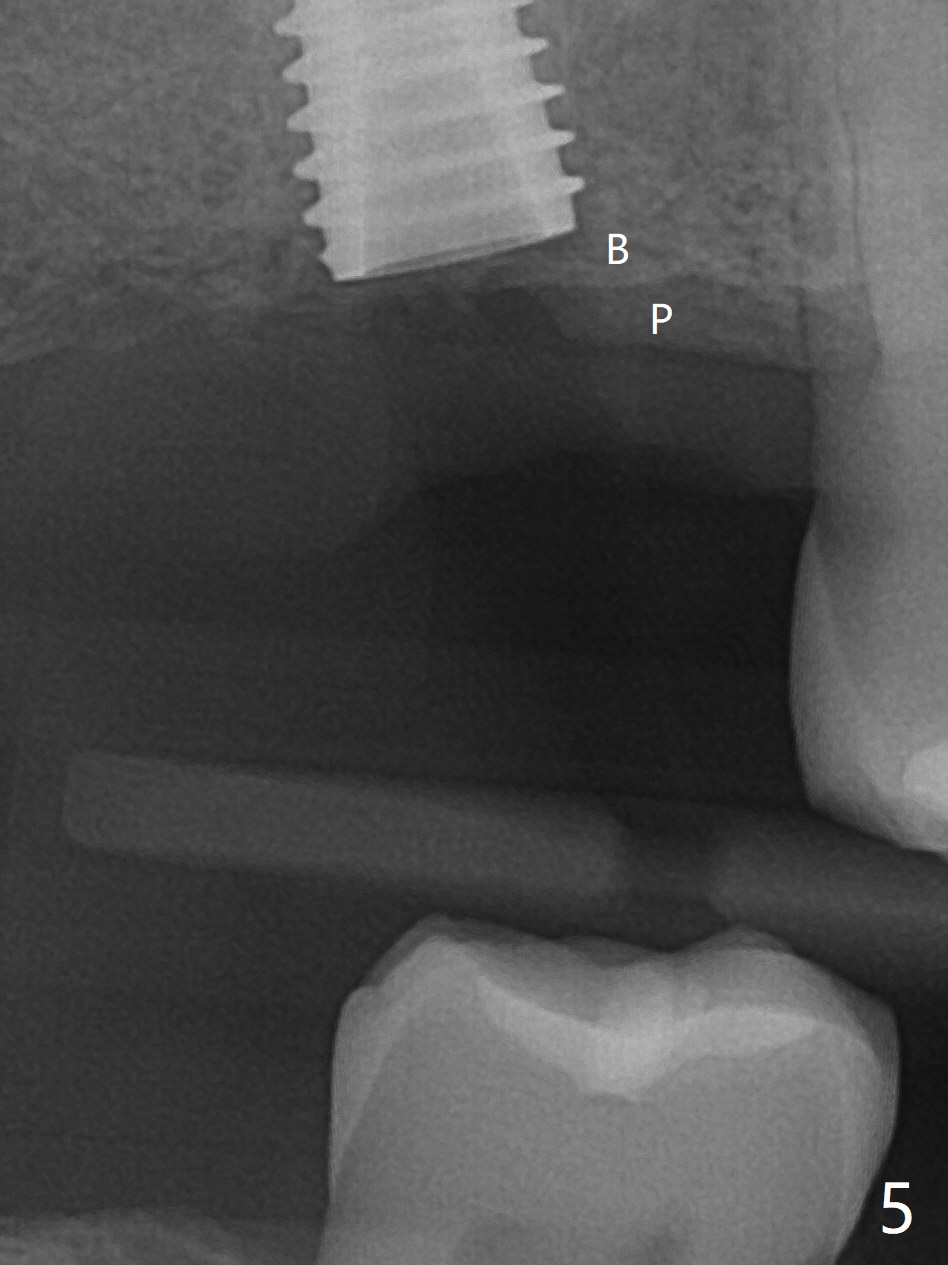

尽管事先准备15号刀片,看到完整2号牙牙槽嵴就舍不得切开。放置以前导板(用于即种),用软组织环形刀做个记号,接着用活检环形刀切取钻洞表面软组织,保存于PRF液体中。术前CT显示3号牙上方粘液囊肿(图一:*),而2号牙上方窦膜薄,总之两者都不好惹(容易感染,窦膜破),提升需要特别小心。完成初步钻洞后,使用17-19毫米长的DIO圆钻,放置粘性骨粉,使用4.5x10毫米报废植体进行提升(到第一横线),结果窦底没有穿(图二:红箭头)。接着使用尖头钻头从原来2.2x5.3毫米一直到3.5x10毫米,几乎每使用一个钻头后都检查窦底完整性,再放置骨粉,使用4.0x10毫米植体提升(到第二横线),好像穿过窦底(图三)。再加骨粉,使用4.5x10毫米植体扭力底,最后放置PRF膜,很难塞入上颌窦,结果只能从钻洞上端近中很小裂口塞入,植入5x8.5毫米正式植体(图四),上颌窦里骨粉呈蘑菇状(*)。临床检查腭侧(P)植体牙槽嵴下,其余骨壁难于判断。而咬翼片却显示植体颊侧(B),腭侧均在牙槽嵴下(图五)。为了减少术后骨质吸收,放置愈合螺帽后(图六:S),植体表面添加骨粉(*),最终把保存的软组织放回原位(二期手术:减少上颌窦与口腔交通,感染),牙周胶水粘固(图七)。术后没有鼻出血。